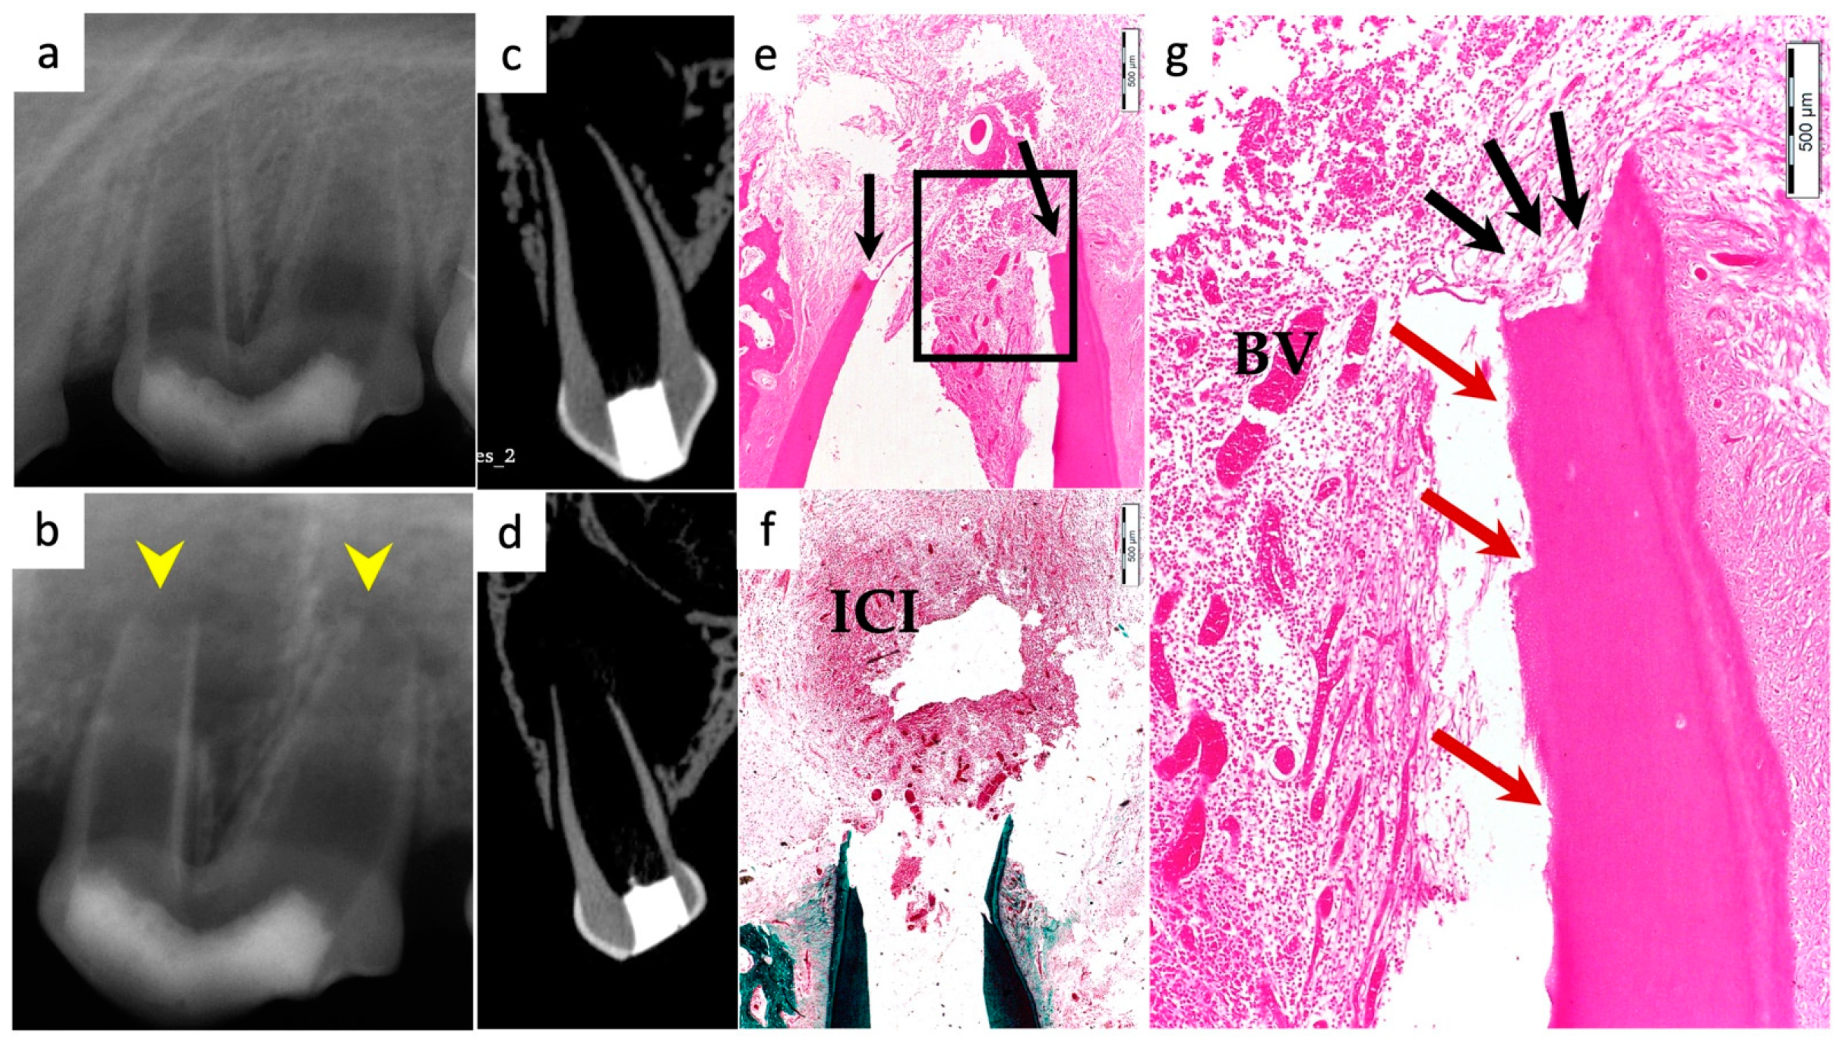

3.4. Degree of Inflammation

3.5. Apical Closure

3.6. Positive and Negative Control Groups